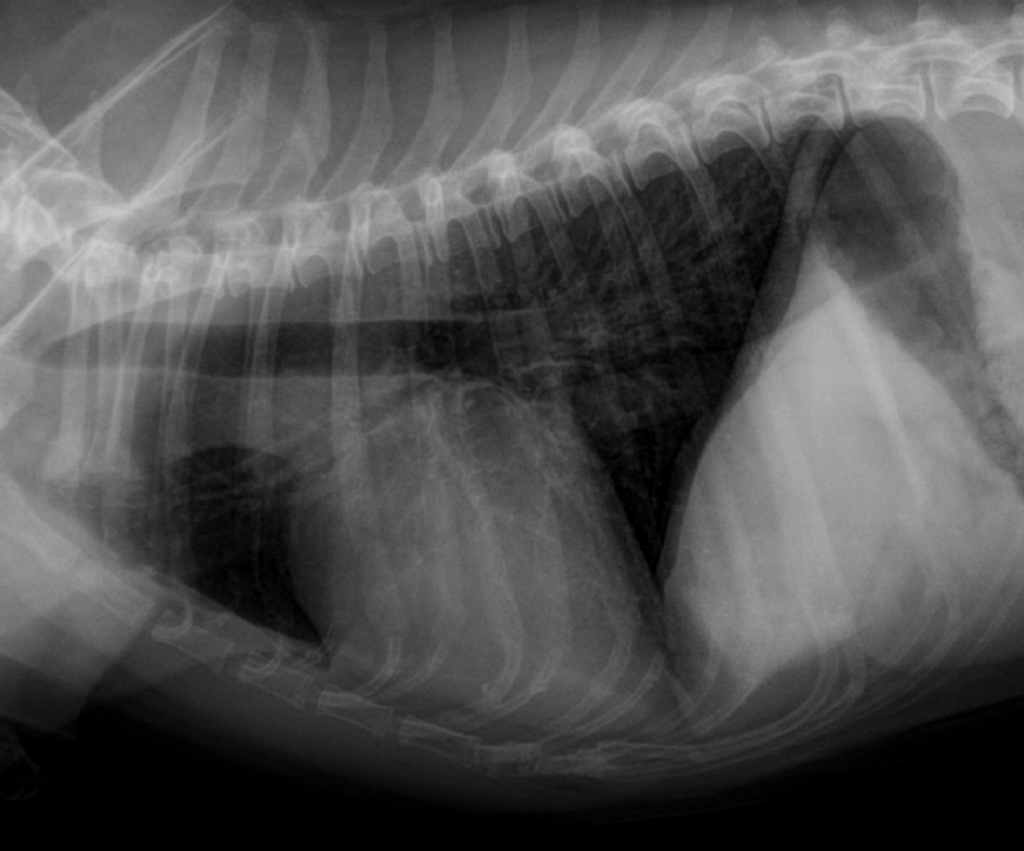

Symptome sind je nach Schwere und Art des Lungenwurmbefalls leichter bis starker Husten bis hin zur Atemnot. Als Folgeschaden einer Infektion mit „Angylostrongylus vasorum“ kann ein Rechtsherzversagen auftreten. Erste Hinweise auf eine Infektion kann bereits ein Röntgenbild des Brustkorbes ergeben – hier erkennt man deutliche Hinweise auf eine mehr oder weniger starke Entzündung der Bronchien (Bronchitis).